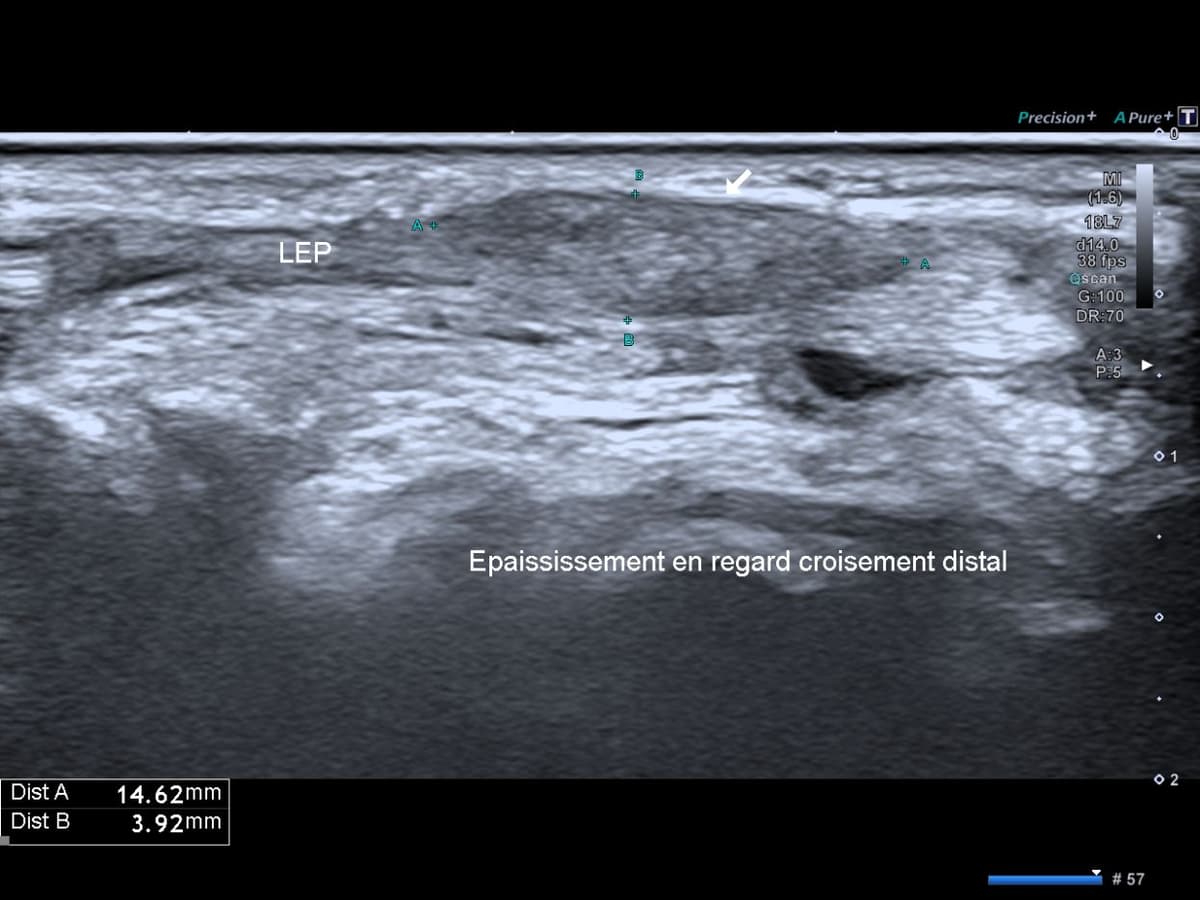

Cas d'une tendinopathie pré-rupture du tendon long extenseur du pouce dans son 3ème compartiment au poignet.

US